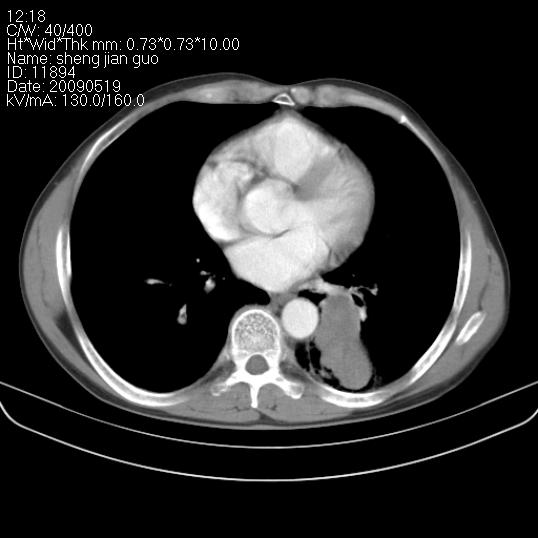

以下是引用zjzjr在2009-5-19 17:25:00的发言:[br]支持楼主考虑,另左肺下叶阻塞性炎症。

以下是引用zhao_bin2008在2009-5-19 17:48:00的发言:[br]支持左肺下叶周围型肺癌并阻塞性肺炎。

以下是引用zsl6918在2009-5-20 7:10:00的发言:[br]左侧中心型肺癌!